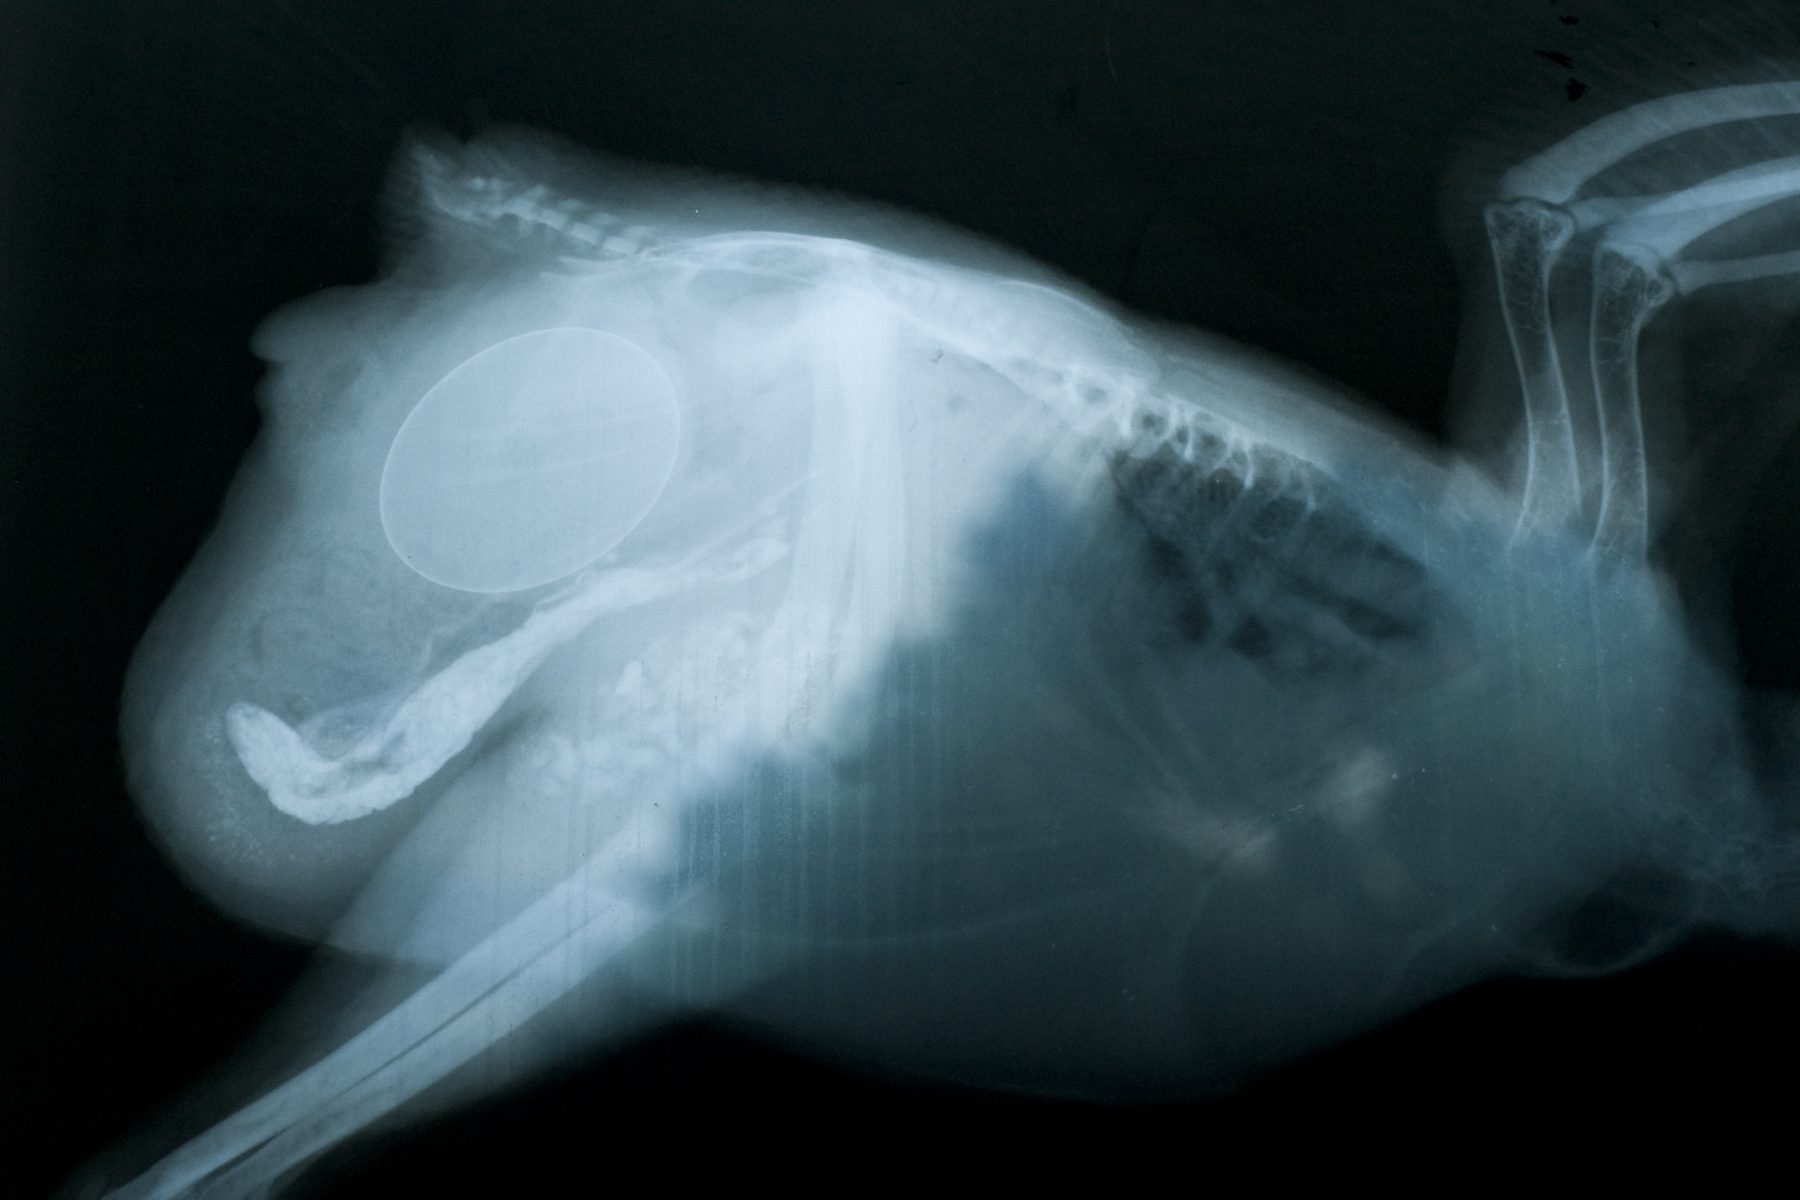

I just wanted to share and ask for thoughts and prayers if you are willing, for my Maxine. I thought she was egg bound, but she ended up laying an egg right before we headed out to the vet. She is swollen below her vent. Eating and drinking and acting normally. We had x-rays and she is staying the night for barium enema studies and blood work.

We are just waiting to hear what the barium study shows. I love this girl so much!!!